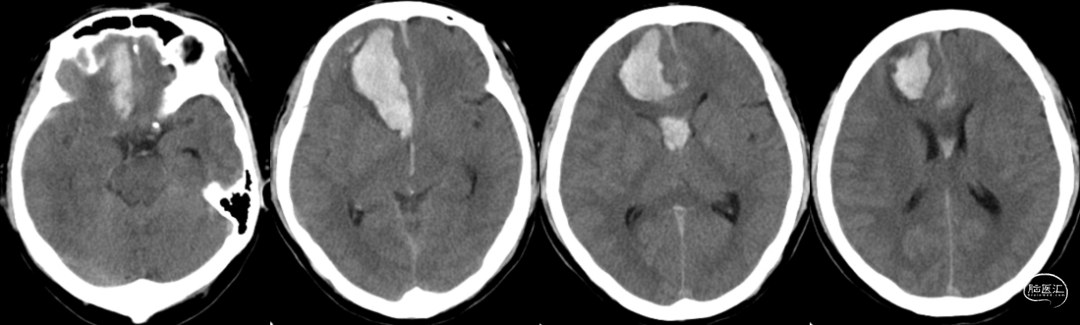

初步诊断:

1. 右侧大脑前动脉多发动脉瘤;

2. 蛛网膜下腔出血、右额叶脑内血肿;

3. 烟雾病;

4. 高血压。